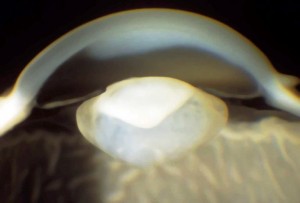

Cataratta

Opacizzazione del cristallino che può essere congenita o svilupparsi progressivamente in età senile. Il sintomo principale è l’abbassamento del visus e l’annebbiamento della vista. Il cristallino catarattoso viene di norma rimosso chirurgicamente e sostituito con un cristallino artificiale (IOL) che ripristina in toto la sua funzione. Le cause possono essere:

Quando l’opacità è localizzata nel nucleo centrale del cristallino (cataratta nucleare) nelle prime fasi si sviluppa la miopia che consente ad un paziente presbite di leggere senza correzione.

Se l’opacità è situata a livello della capsula posteriore del cristallino (cataratta sottocapsulare posteriore) influenza negativamente la vista ed è particolarmente fastidiosa se il paziente è esposto alla luce molto forte.

L’intervento di cataratta è raccomandato quando il visus massimo corretto è uguale o inferiore a  4/10 o quando la menomazione soggettiva visiva impedisce attività necessarie come la guida o la lettura. Anche l’abbagliamento disabilitante può costituire un’indicazione all’intervento ed è più comune nelle cataratte sottocapsulari posteriori.

Cataratta congenita

Patologia che rende opaco il cristallino già alla nascita o entro i primi 3 mesi di vita. Ancora oggi rappresenta una delle cause più frequenti di cecità nell’infanzia, con un’incidenza compresa tra il 10 e il 15%. Nei 2/3 circa dei casi è bilaterale e diverse sono le cause: